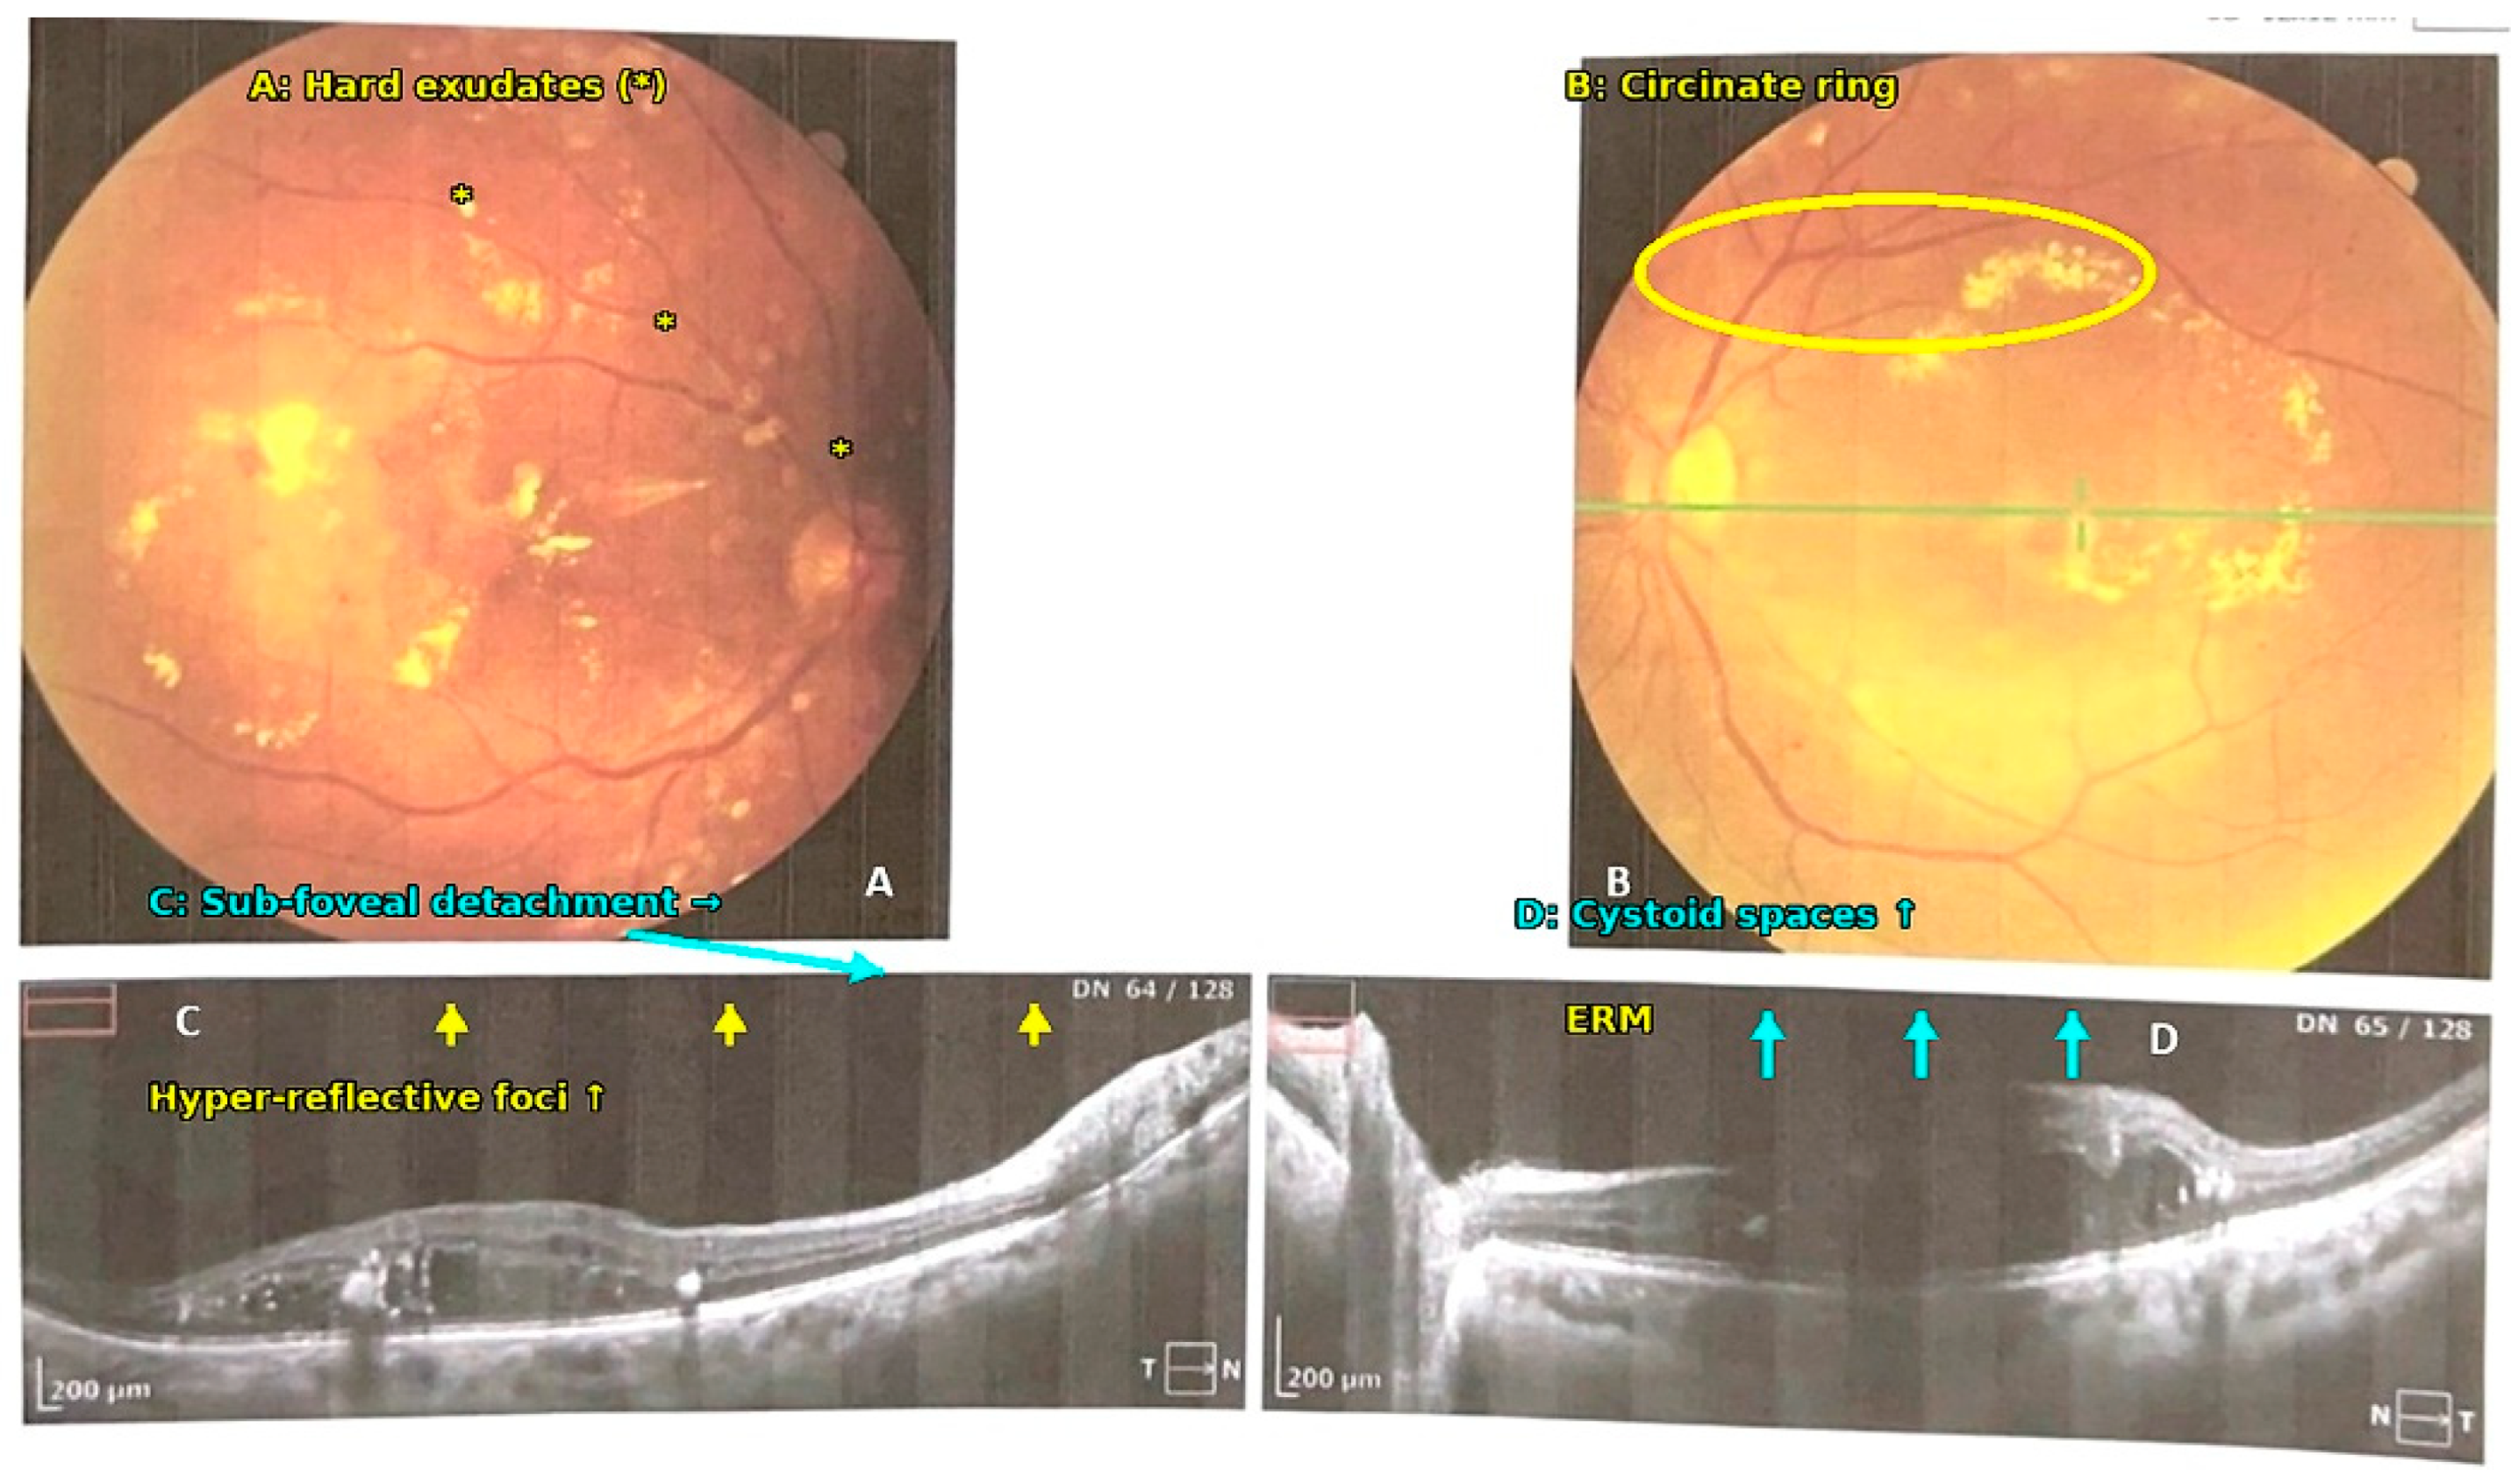

1. Introduction

2.6. Ophthalmic Evaluation

2.7. Optical Coherence Tomography